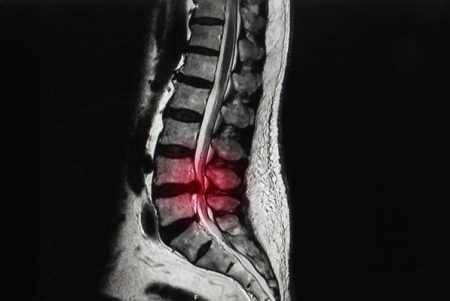

تنگی کانال نخاعی وضعیتی است که با باریک شدن کانال نخاعی مشخص می شود که بر نخاع و اعصاب فشار وارد می کند. این باریک شدن می تواند در گردن (تنگی ستون فقرات گردنی) یا کمر (تنگی ستون فقرات کمری) رخ دهد. شایع ترین علل تنگی کانال نخاعی عبارتند از:

• فتق دیسک: وقتی هسته داخلی دیسک ستون فقرات بیرون زده و روی کانال نخاعی فشار می آورد، می تواند باعث تنگی شود.